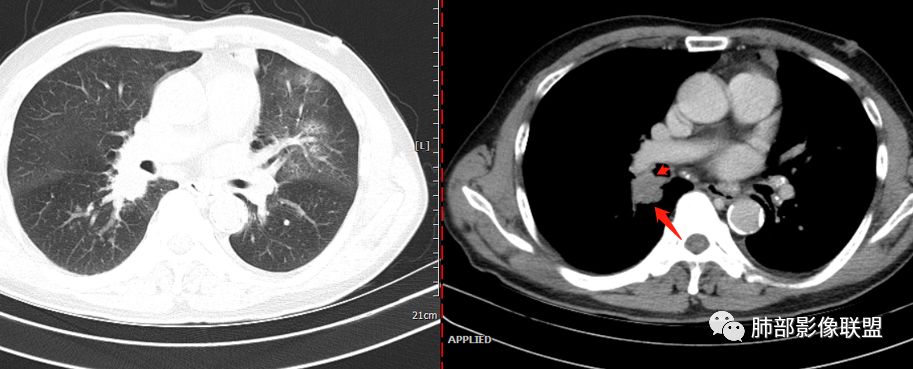

单从影像看,:右肺下叶背段结节并支气管闭塞,肿瘤可能性大;右肺底结节,强化较明显,考虑肉芽肿性病变;左肺上叶大片间质性改变,考虑感染病变;临床提示CRP增高,贫血,糖尿病,单核略高,IGE增高。一元论不好解释。

左上肺大片网格状影,内有实变,内支气管有狭窄和扩张,血管模糊,右下肺有大小多发结节,纵隔有多发淋巴结,部分钙化,还是把肿癌放前面,腺癌?

老年男性,反复咳嗽咳痰十余年,加重伴发热5天,胸痛2天。既往有糖尿病病史。白细胞不高,肝功能受损,CRP及igE明显增高。左肺上叶大片磨玻璃影伴局部实变,支气管通畅,右肺下叶背段近端支气管旁不规则实性结节,轻度均匀强化,背段支气管受压变窄,纵隔及双肺门多发淋巴结肿大并钙化。考虑左上肺感染性病变,先抗感染复查,继续查病原体。右下肺背段结节建议经TBLB活检,排外肿瘤。

胸CT:左肺上叶前段实变,其周围及左肺上叶尖后段可见肺气肿背景下渗出性病变,病灶内可见支气管扩张,气道壁呈不规则增厚,双肺散在小结节状影;右肺下叶结节影,内可见空泡,边缘模糊,不规则。增强可见病灶内血管造影征,右肺门增大,纵隔淋巴结多发肿大。

左肺上叶病灶长轴与支气管走形一致,提示沿支气管分布病变,倾向于炎性,大家可能怀疑这个病例是来源于胸膜下为主的,胸膜下来源首先整体是来源于胸膜下,与胸膜下之间没有间隙,而这例与胸膜下有间隙。而且这个病变是沿支气管朝外蔓延的,而胸膜下来源的是朝内蔓延的,唯一给我们错觉的是靠近纵隔胸膜这个地方有问题。但是靠近纵隔胸膜这个位置实变不是靠近胸膜实变,它边缘收缩的,没有膨隆的迹象。我们看到里面支气管直达远端稍扩张,是以中央间质为主、小叶间隔朝外蔓延,有间质也有实质病变,走向是沿中央间质方向走的,我个人倾向炎性病变。    问题是右下叶病灶怎么解释?右隔上、右肺门各有一个结节。这个病人有急性咳嗽、胸痛的病史,还有糖尿病病史,周围渗出比较明显,应该警惕炎性病变,要警惕克雷伯杆菌、结核、金葡菌霉菌,因为糖尿病人经常好发这些病菌感染。那么右下叶病变怎么考虑?能不能一元论?    左肺病灶是一个急性渗出为主的病变,一个急性感染的迹象;右肺下叶背段结节,没有看到支气管,增强图支气管壁增厚,局部小结节,呈分叶状,支气管堵塞,没有粘液栓样指套样改变,但是里面有强化,我倾向于癌,其次待排结核。我还是倾向于癌的可能性,恶性可能性大一些,可惜我看不到支气管腔内。还考虑有没有淀粉样变性的问题,弥漫钙化灶最常见的一个是结核,另一个是淀粉样变性。叶段支气管壁有弥漫增厚的迹象。所以淀粉样变性跟结核都要考虑。